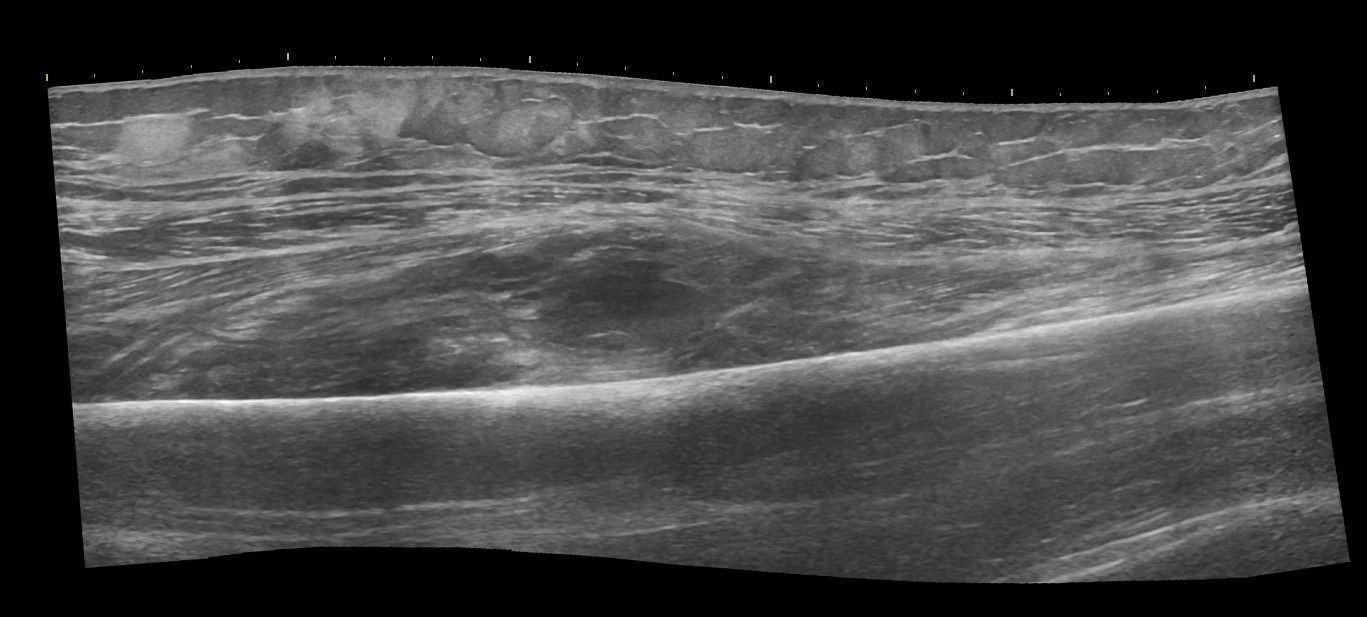

- Διάγνωση Μυϊκών Βλαβών: Το Υπερηχογράφημα Μυών επιτρέπει την αναγνώριση μυϊκών παθήσεων όπως τα αιματώματα, τα λιπώματα, τα νεοπλάσματα και η σημειολογία ασβεστοποιού μυοσίτιδας.

- Δυναμική Εξέταση: Με το Υπερηχογράφημα Μυών μπορούμε να παρατηρήσουμε τους μύες κατά τη διάρκεια διαφόρων κινήσεων, κάτι που μας επιτρέπει να ανιχνεύσουμε μυϊκές ανωμαλίες που ενδέχεται να μην είναι ορατές σε στατικές εικόνες.

- Διάγνωση Μυϊκών Κηλών: Λόγω της δυναμικής εξέτασης, το Υπερηχογράφημα των Μυών είναι η μόνη απεικονιστική μέθοδος που επιτρέπει τη διάγνωση των μυϊκών κηλών.